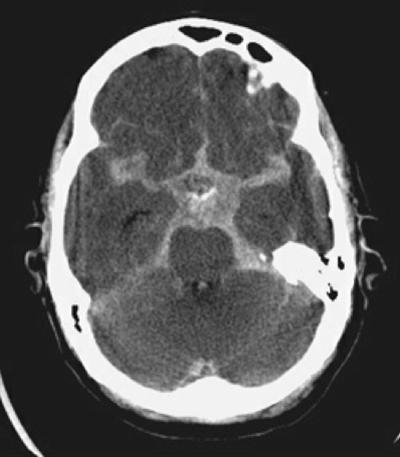

Step 2: Cisterns

Cisterns

Cisterns are the compartments within any of the openings in the subarachnoid space of the brain filled with cerebrospinal fluid. Two key questions to answer regarding the four key cisterns (Circummesencephalic, Suprasellar, Quadrigeminal and Sylvian)

• Is there blood?

• Are the cisterns open?